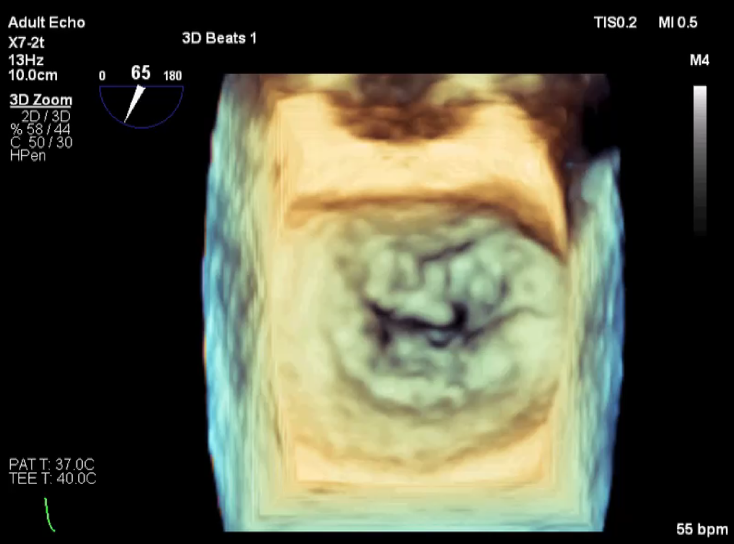

3D视图打开夹子

3D视图下观察二尖瓣双孔形态

3D-color:残余少量返流